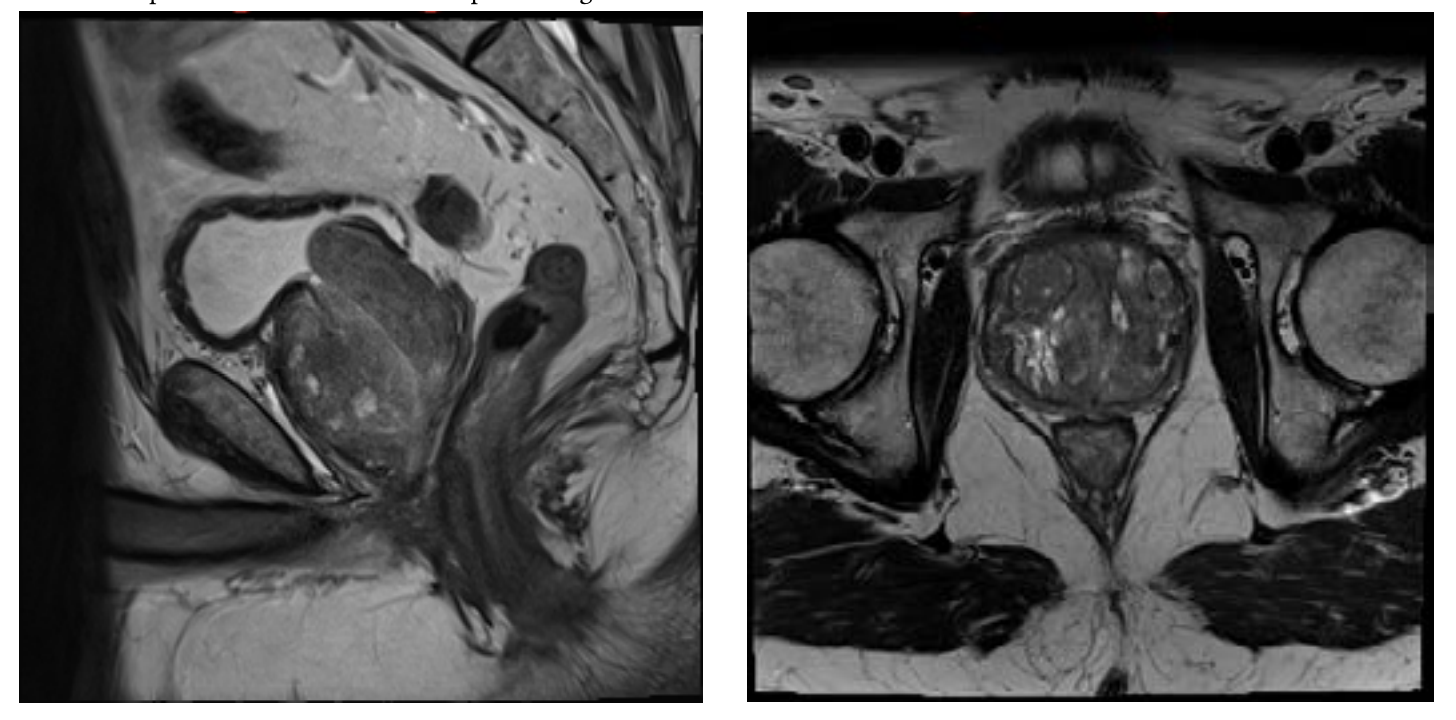

A 74-year-old male with past medical history of hypertension, coronary artery disease, and BPH with LUTS refractory to medical management presented for evaluation. The patient underwent an MRI of the prostate demonstrating a 182 cc gland with an enlarged transitional zone measuring 144 cc (Figure 1). The patient’s baseline IPSS and QoL were 18 and 5, respectively. Given the patient’s prostate gland size, and medical comorbidities, he elected to undergo PAE for management of his LUTS. On the day of his PAE, right common femoral arterial access was obtained and a pigtail DSA was obtained delineating pelvic arterial anatomy. On the right, the prostatic artery arose from a vesiculoprostatic trunk, with a shared origin with the superior vesicular artery (Figure 2). This was selectively catheterized with a progreat alpha microcatheter (Terumo, Tokyo, Japan), and 016” fathom microwire (Boston Scientific, Marlborough, MA). Angiography demonstrated perfusion of the entire right portion of the gland, without evidence of extra-prostatic supply (Figure 3). Embolization was performed with 300-500 micron Embospheres (Merit Medical, South Jordan, UT) to stasis. On the left, the prostatic artery arose from the left obturator artery (Figure 4). This was subsequently catheterized with the same catheter/wire combination, with angiography demonstrating left glandular perfusion without extra-prostatic supply (Figure 5). Embolization was again performed to stasis with 300-500 micron Embospheres. The patient did well post-procedurally with self-limited urinary frequency and dysuria for 3 days. By 3 months post PAE, the patient reported a significant improvement in his LUTS, with an IPSS/QoL of 3 and 0, respectively.

The patient had a long-term response to PAE for approximately 5 years, at which point he experienced gradual recurrence of his LUTS. He re-presented with an IPSS/QoL of 27/5, respectively. At this point, repeat MRI of the prostate was obtained demonstrating a total gland volume of 119 cc, with a transitional zone volume of 94 cc (Figure 6). Given his recurrence of symptoms, and enlarged gland not amenable to standard surgical therapies, he elected to undergo repeat PAE.